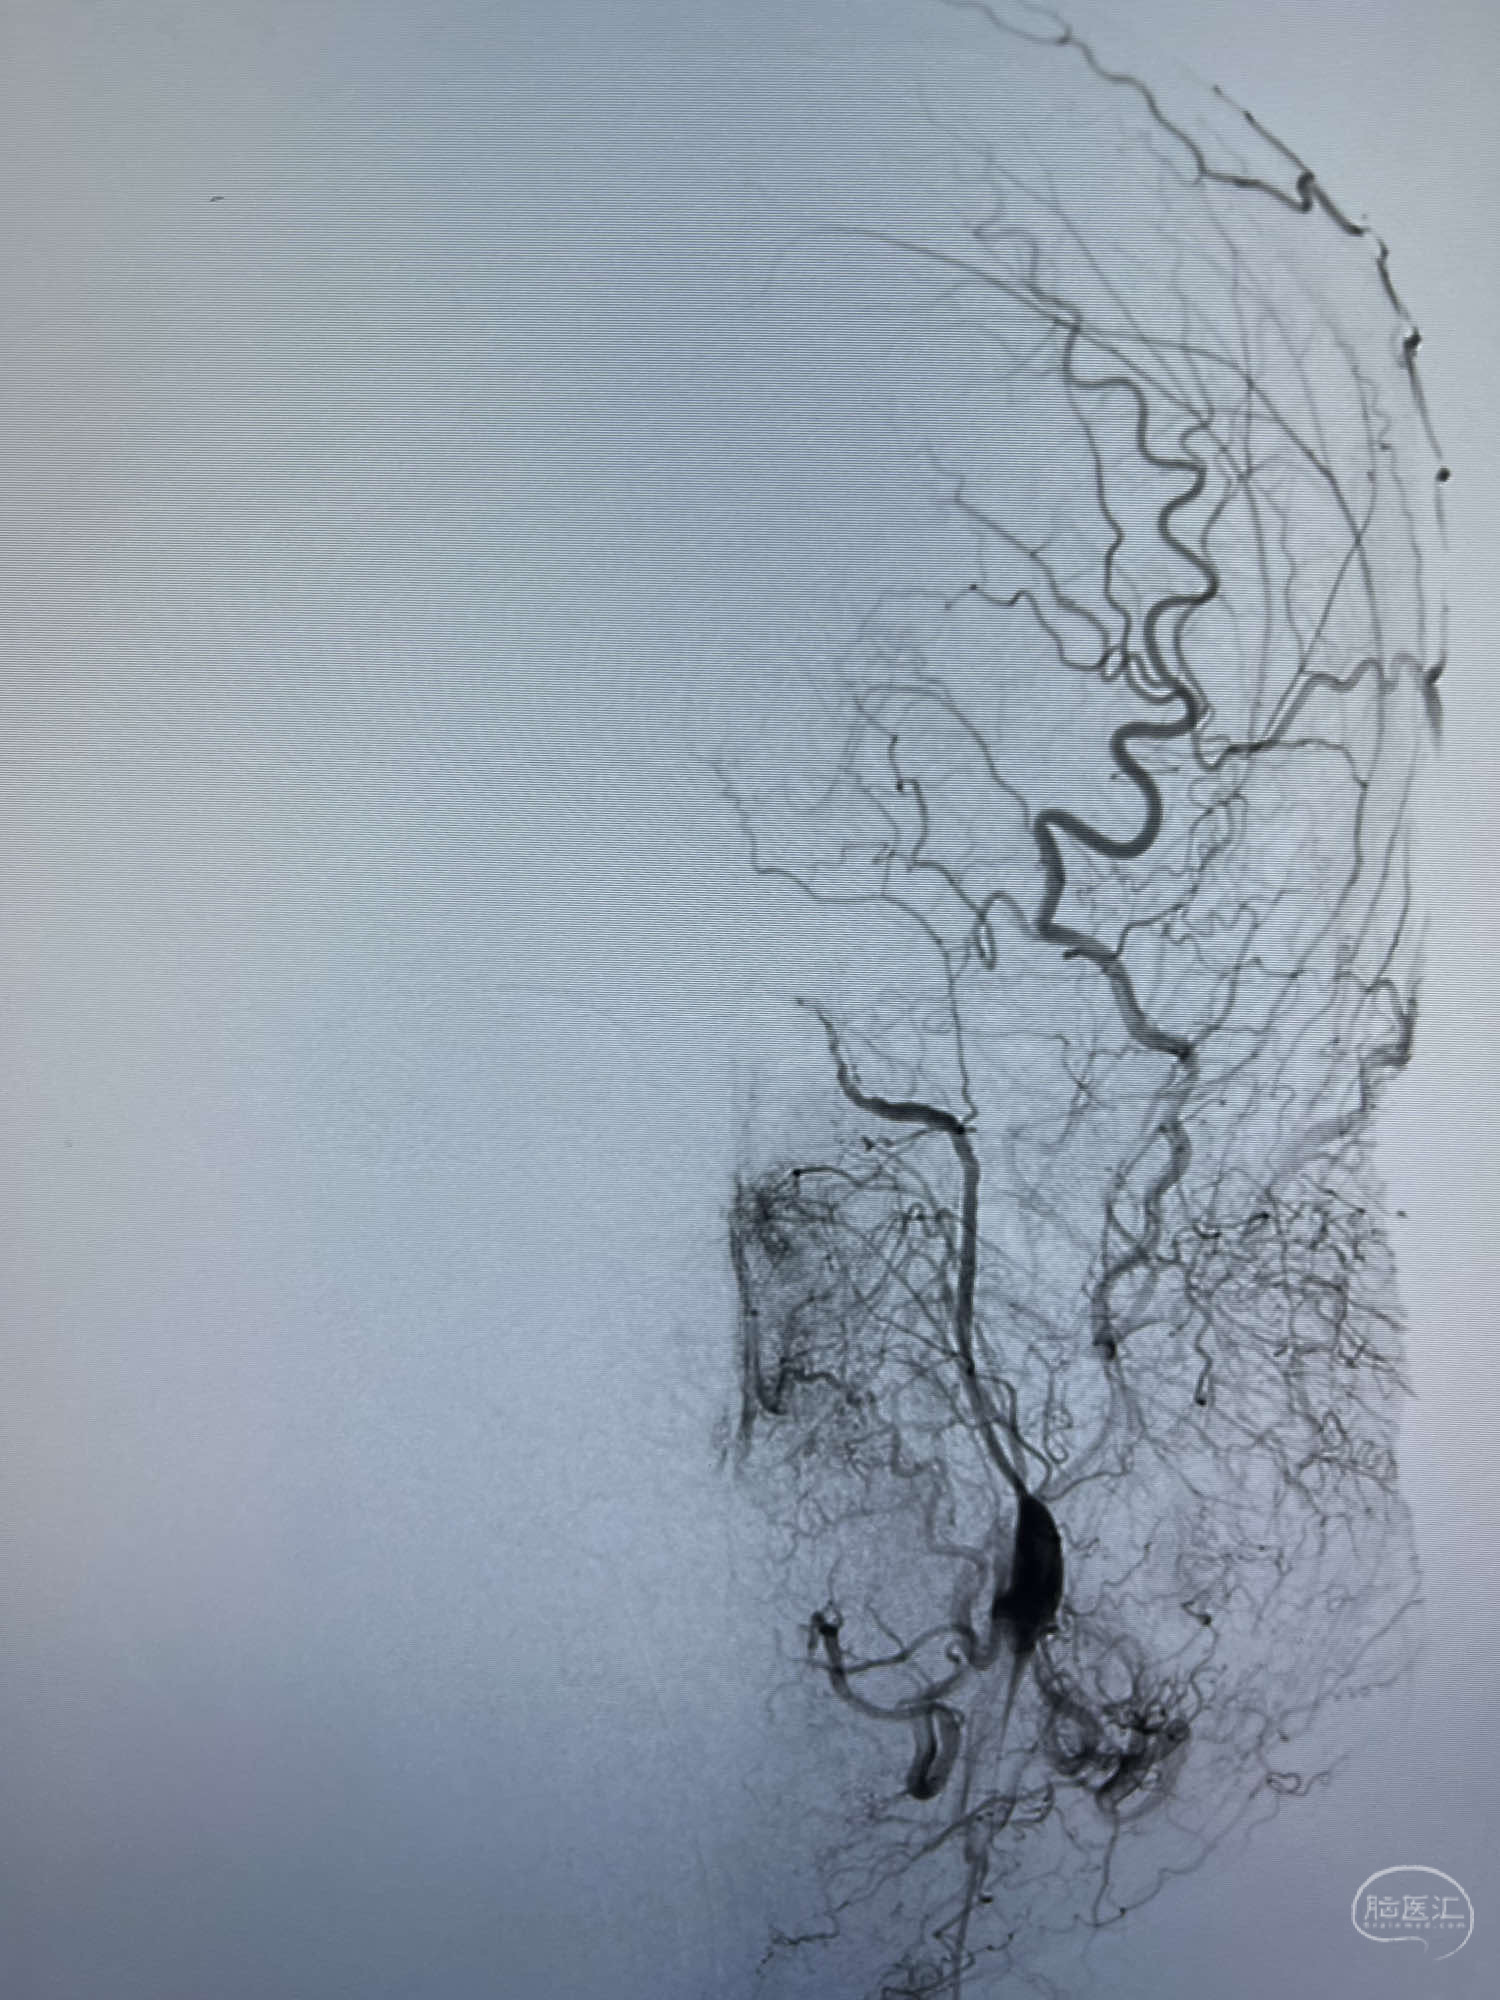

DSA示:左侧颈内动脉眼动脉段以远闭塞,后交通动脉开放,椎基底动脉通过后交通动脉代偿左侧大脑中动脉区域,右侧发出双侧大脑前动脉,右侧大脑中动脉M1末端宽颈动脉瘤,大小约4.3mmx4.6mm。

6F Neuromax➕6F115cm 心玮中间导管建立路径,sychro14微导丝➕VIA21超选至动脉瘤体内近中部,WEB5mmx3mm植入动脉瘤。

WEB瘤内扰流装置5mmx3mm经过“种子、萌芽、开花”三个阶段,打开后良好贴壁,动脉瘤内血液滞留,载瘤动脉通畅。WEB一步到位,通过瘤内扰流的方式起到栓塞动脉瘤的作用,避免了应用支架保护分支血管,简化了操作步骤,降低了术中血栓及出血的风险。